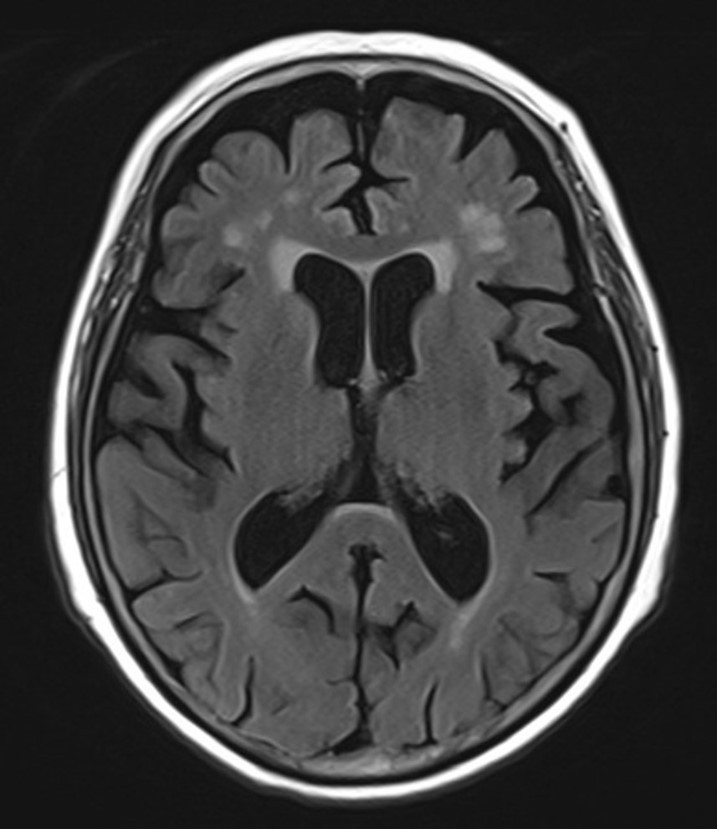

뇌 MRI도 찍고 인지기능 검사도 여러 가지 했는데

결과를 보는 순간... 솔직히 조금 놀랐어요.

뇌경색은 없었지만

뇌가 나이에 비해 상당히 위축되어 있었고

인지기능 검사 점수도

정상 범위를 벗어나 있었습니다.

그림3.jpg 촬영 일시: 2025.04.19

<Fig 1. 뇌 MRI>

33세에 경도인지장애 단계라니...